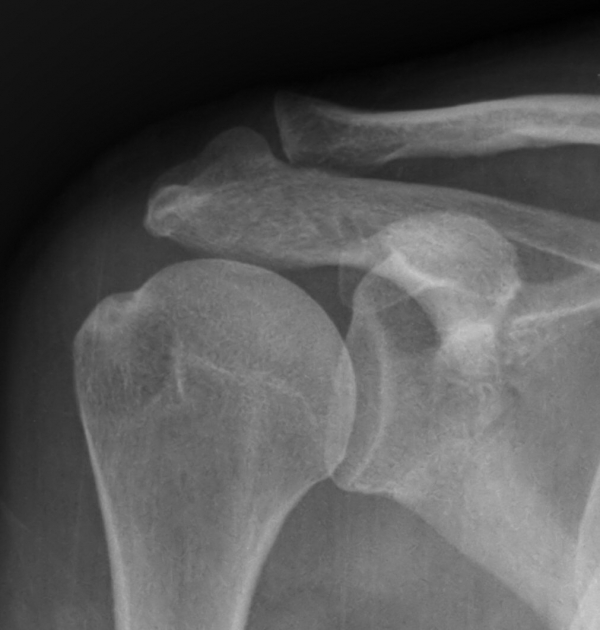

´Ü¼ø¹æ»ç¼±°Ë»ç

´ë°áÀý°ú °ßºÀÇϺο¡ ¹æ»ç¼± Åõ°ú¼º °¨¼Ò(sclerosis)°¡ °üÂûµÈ´Ù(÷ºÎÆÄÀÏ).